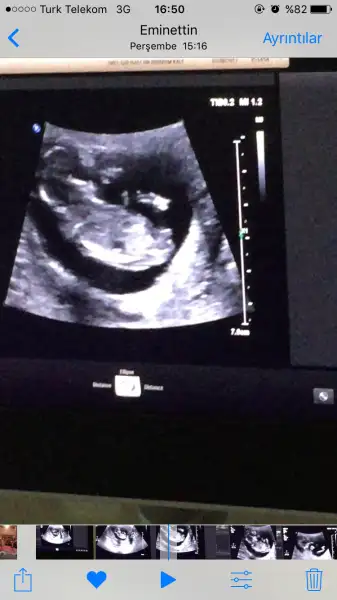

Göründüğü gibi %100e yakın oğlum olacak

Kardeşim bu videoyu çekerken doktor erkek dediğinde 'yaaa hayırrrr' diip bana da tüh sana gibi el işareti yapıyor